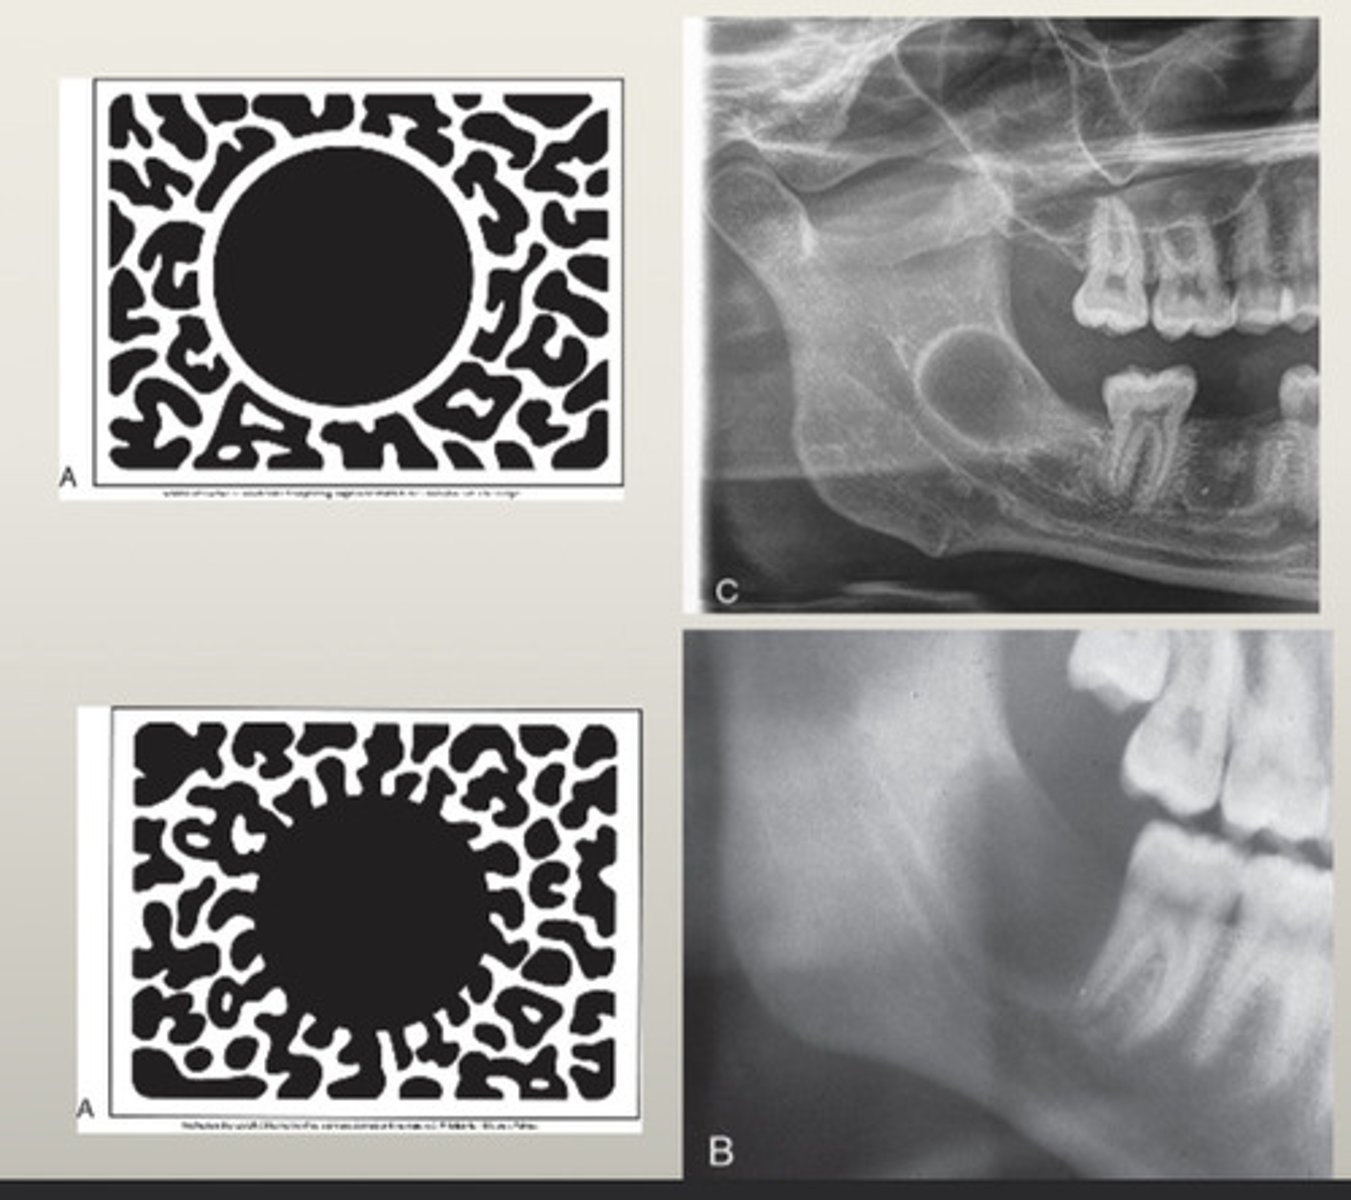

What are unilocular radiolucent lesions?

Cysts, benign tumors

What is the growth rate of unilocular benign tumors?

Slow growing

What characterizes non-corticated lesions?

Fast growing, nonvital teeth

How is a radicular cyst described radiographically?

Well corticated